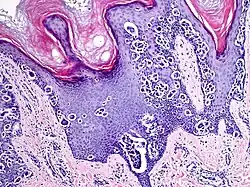

Additional image

Melanocytic acral nevus with intraepidermal ascent cells (MANIAC)